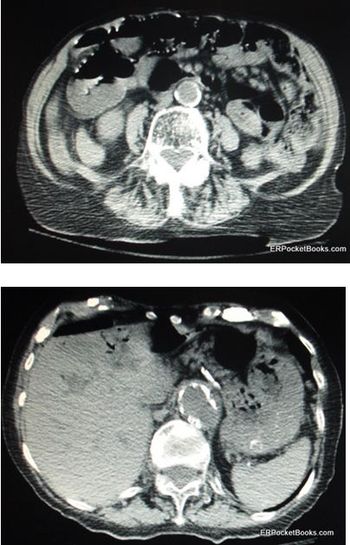

Symptoms have been present for 2 days. Lab studies are notable for BUN (43 mg/dL) and CO2 (21 mmol/L). The real problem is visible on CT of the abdomen and pelvis. Your diagnosis?

At risk for mesenteric ischemia-an uncommon but feared cause of abdominal pain-are the elderly and chronically ill.